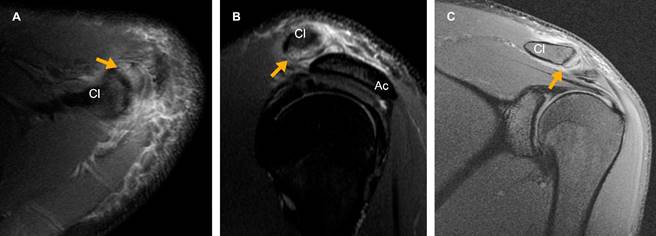

En la RM se observa edema óseo del extremo distal de la clavícula, edema de los tejidos blandos periarticulares (Figura 1) y ruptura del ligamento acromioclavicular superior con discreto incremento del espacio de 7.5 mm (Figura 2).

Figura 1: Edema del extremo distal de la clavícula (Cl). Imágenes ponderadas en densidad de protones con saturación grasa en planos A) axial, B) sagital y C) coronal que muestran incremento en la intensidad de señal (flecha amarilla) del extremo distal clavicular. B) El acromion (Ac) conserva su intensidad de señal normal.